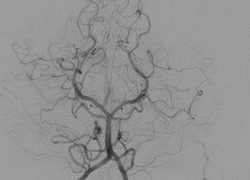

血管の疾患 ~ 動脈瘤・動脈撮影

動脈瘤(aneurysm)動脈瘤には外傷性動脈瘤traumatic aneurysmと病的動脈瘤pathologic aneurysmの二つがあります。外傷性動脈瘤:創傷や動脈内注射時における血管損傷の継発症です。損傷部に拍動性血腫が生じ、...